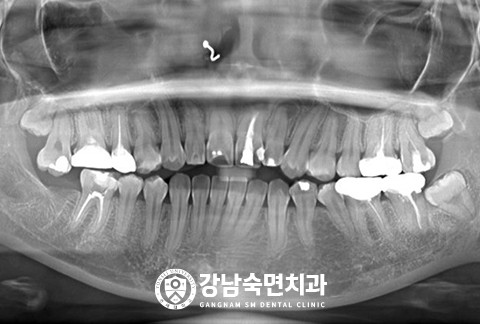

임플란트-전후사진